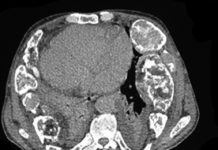

(RSNA) Three-dimensional (3D) volume-rendered reconstruction from a CT Chest scan shows the distribution of the ground-glass opacities. Images in a 41-year-old woman who presented with fever and positive polymerase chain reaction assay for the 2019 novel coronavirus (2019-nCoV). Source: Liu, et al, Radiology 2020.